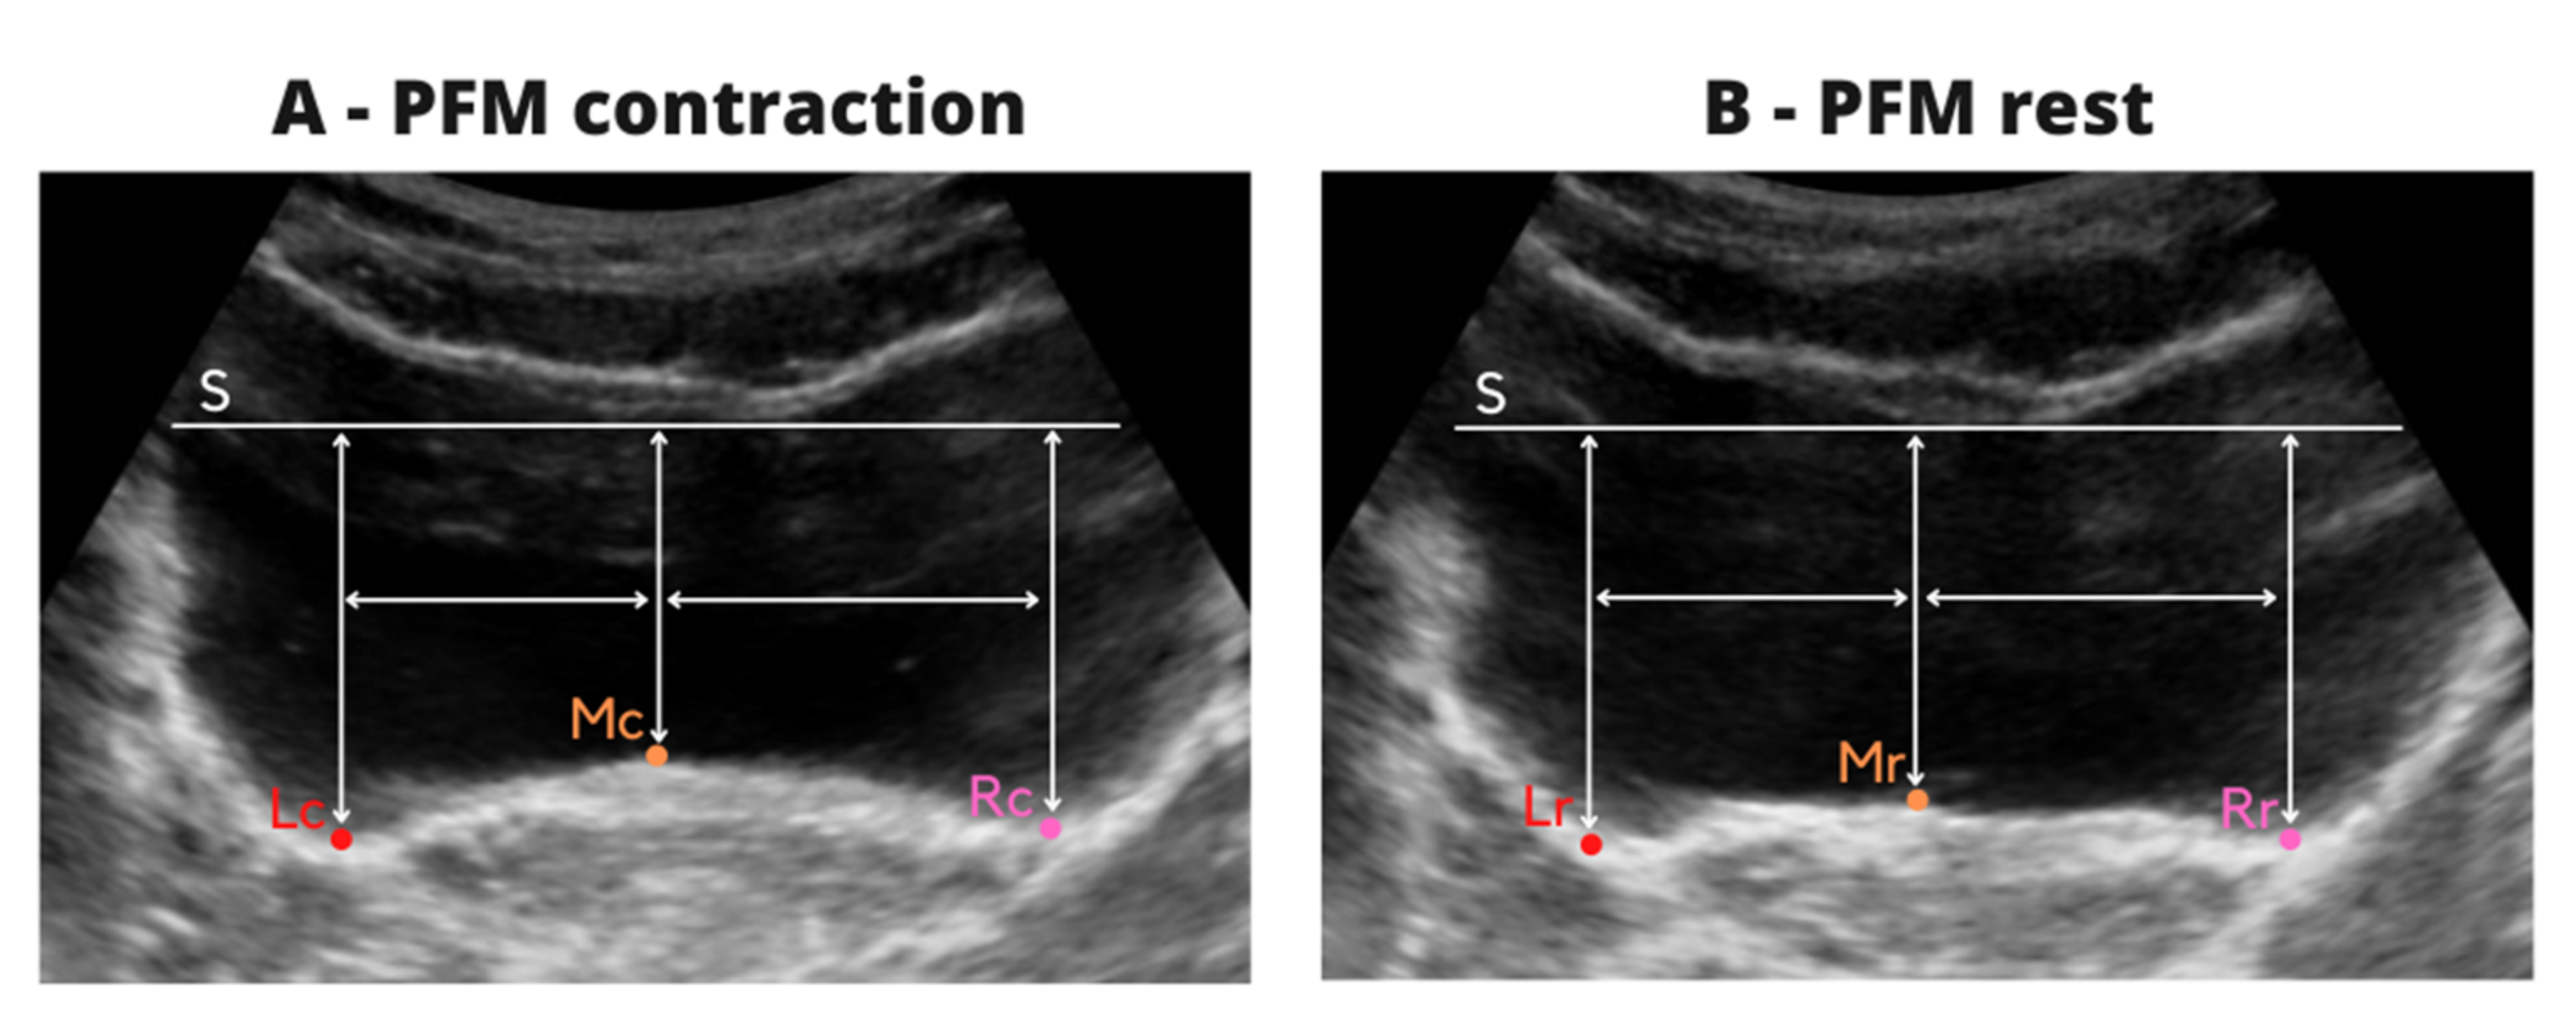

A horizontal tangent (S) was drawn with respect to the lowest point of the bladder apex on both images at the same level. The S line was a reference and then the distance was measured between following points (Figure 2A):

Figure 2.

Description of ultrasound image analysis during contraction (A) and rest (B).

- -

- horizontal tangent (S) and the highest point at the middle of the bladder base (MC),

- horizontal tangent (S) and the lowest point of the bladder base to the left (LC) and right (RC) of the MC point,

- the distance between the MC to LC and MC to RC points was measured and then, the mean value from two images was calculated. This procedure allowed marking of the three points on the bladder base on resting images at the same location, and to calculate the reliability of resting evaluation at the same points as the reliability of contraction.

The same procedure was repeated for the resting images.

A horizontal tangent (S) was drawn on each of the images with respect to the lowest point of the top of the apex of the bladder, and then the distance was measured between the following points (Figure 2B):

- horizontal tangent (S) and the highest point at the middle of the bladder base (MR),

- horizontal tangent (S) and the LR point—located at the base of the bladder to the left of the MR point corresponding to the distance between the points MC–LC on the images from contraction,

- horizontal tangent (S) and the RR point—located at the base of the bladder to the right of the MR point corresponding to the distance between the points MC –RC on the images from contraction.